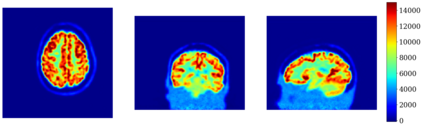

In this work, we investigate hybrid PET reconstruction algorithms based on coupling a model-based variational reconstruction and the application of a separately learnt Deep Neural Network operator (DNN) in an ADMM Plug and Play framework. Following recent results in optimization, fixed point convergence of the scheme can be achieved by enforcing an additional constraint on network parameters during learning. We propose such an ADMM algorithm and show in a realistic [18F]-FDG synthetic brain exam that the proposed scheme indeed lead experimentally to convergence to a meaningful fixed point. When the proposed constraint is not enforced during learning of the DNN, the proposed ADMM algorithm was observed experimentally not to converge.